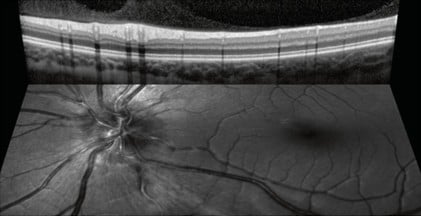

Confocal Scanning Laser Ophthalmoscopy (cSLO)

The SPECTRALIS® confocal scanning laser ophthalmoscope (cSLO) is an innovative technology for imaging the retina. The cSLO provides image detail and clarity not available from fundus photography by combining the selectivity of laser light with the pinpoint resolution of confocal scanning. Often the technology reveals critical diagnostic details not visible with traditional ophthalmoscopy, helping the clinician to document clinical findings. Since cSLO imaging minimizes the effects of light scatter, it can be used effectively even in patients with media opacities or small pupils.